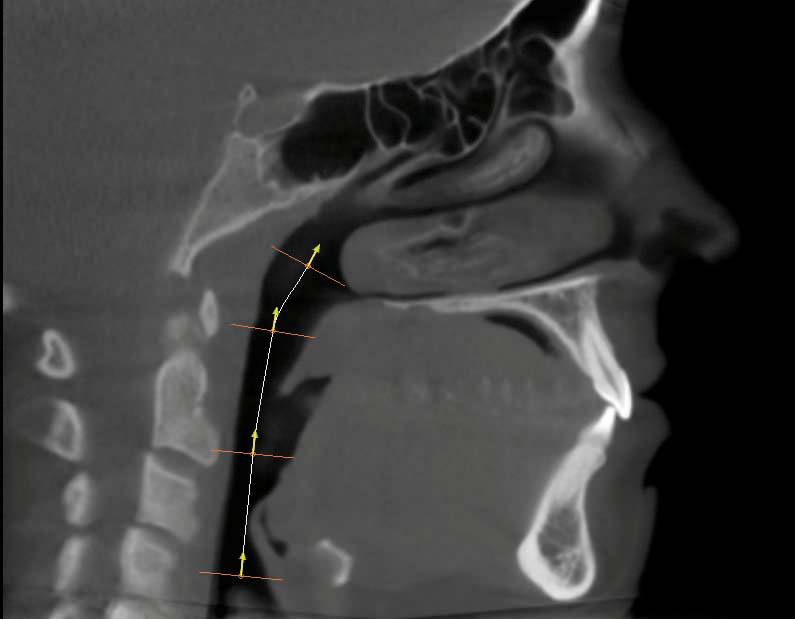

j. The "Airway" image is created in the "Volume Render" tab by selecting the "Airway Measurement" icon at the top of the screen and choosing "Volume Render" from the "Reconstruction" drop-down menu located in the upper left corner of the screen.

The skull will automatically orient for optimum airway marking. To begin measuring, begin at the base of the airway and click inside the airway passage to place several points moving upward. Right click to finish at the height the doctor determines should be used for every patient when measuring airway.

You might then want to switch from the "Gray Scale" view to the "Soft Tissue + Bone 1" view using the icons on the left side of the screen.

As described in step 7, "Capture to Gallery" and name the image "Airway."